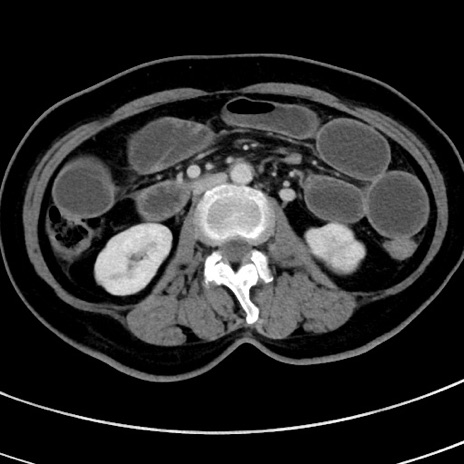

冠状断像

【症例】 60歳代女性

【主訴】むかつき、みぞおちの痛み

【現病歴】3日前よりむかつきがあり、食事がとれない。

【既往歴】糖尿病

【身体所見】発熱なし、心窩部圧痛軽度あるも、腹膜刺激症状なし。

【データ】WBC 7400、CRP 1.92